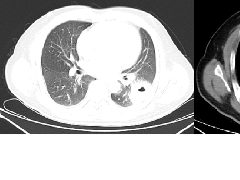

2、病灶常有一个主病灶,常位于下肺。后沿气道播散为多发病灶。

3、重力作用,叠瓦征。近叶间裂因重力效应,呈膨隆改变。

5、支气管粗细不均,呈“枯树枝征”,但与肺炎这一点鉴别不具有统计学差异。可发生支气管扩张

6、空腔形成,部分蜂窝状改变。

8、斑片常伴有结节,边缘清楚GGO或欠清楚。